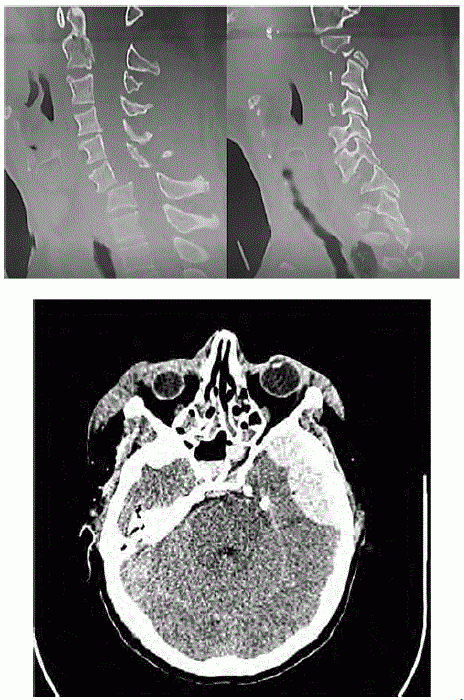

Uma paciente de 27 anos de idade, com 63 kg, previamente hígida, é levada ao hospital pelos bombeiros, em imobilização padrão, após colisão do próprio carro em uma árvore. Queixa-se de cefaleia, cervicalgia e desconforto em ombros/membros superiores. Ao exame inicial, constatam-se AC = RC2T com BNF; FC = 110 bpm; AP = MVF sem RA; FR = 18 irpm; PA = 140 mmHg x 90 mmHg; e SatO2 = 99%. Na avaliação inicial, apresenta abertura ocular espontânea, pupilas isofotorreagentes, com colar cervical, fala confusa, amnésia lacunar e dor à palpação da coluna cervical, obedecendo a comandos, porém com dificuldade de mobilizar braços (força distal 1 e força proximal 4, em ombro e braço direito, e grau 3 à esquerda), com força aparentemente preservada em pernas. É realizada a tomografia computadorizada (TC) de crânio e coluna cervical, segundo as imagens apresentadas.

A respeito desse caso clínico e com base nos conhecimentos médicos correlatos, julgue os itens a seguir.

A TC de coluna cervical evidencia uma fratura-luxação C6-C7 classificada como tipo B2-F2, de acordo com a AOSpine.

A paciente possui indicação de neurocirurgia de urgência para drenagem do hematoma temporal e colocação de tração cervical.

A paciente encontra-se em Glasgow 14 e Frankel B.